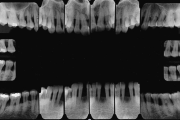

Krooniline parodontiit on mikroobide poolt põhjustatud hammaste tugikudede põletik, mille tulemusena tekib progresseeruv alveolaarluu (nähtav röntgenograamil) ja periodontaalligamendi destruktsioon, igemetaskute moodustumine, igeme retsessioon või mõlemad kahjustused kombineeritult. Loe edasi »

- luu destruktsioon (5)

- hammaste asukoha muutus (5)

- vertikaalne luukadu (2)

- horisontaalne luukadu (3)

- hamba kinnitussidemete kadu (3)